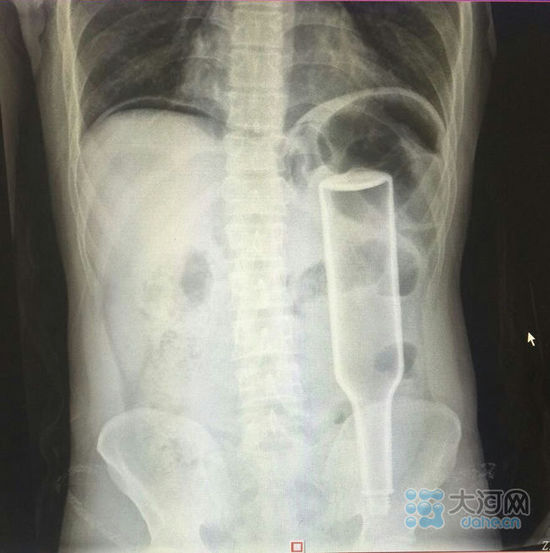

看這片子,花露水瓶子已經(jīng)很“深入”了。

大河網(wǎng)訊在鄭州務(wù)工的外地男子王某,下班到家后閑著沒事兒干,于是將一個長18厘米的花露水瓶子塞進了自己的肛門,不過因為用力過猛,快感沒來,瓶子卻把直腸給戳破了,疼得受不了了,王某羞答答地來到鄭州人民醫(yī)院就診,醫(yī)生給他做了手術(shù),現(xiàn)在已經(jīng)出院。